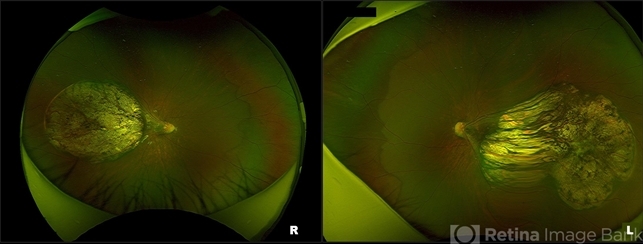

- Bilateral Macular Colobomata With Temporal Dragging of Optic Disc

- bilateral macular colobomata, temporal dragging of optic disc

- Optos UWF Daytona Plus

- Optos ultra-widefield retinal image of a 7-year-old male child showing bilateral macular colobomata with temporal dragging of optic disc.